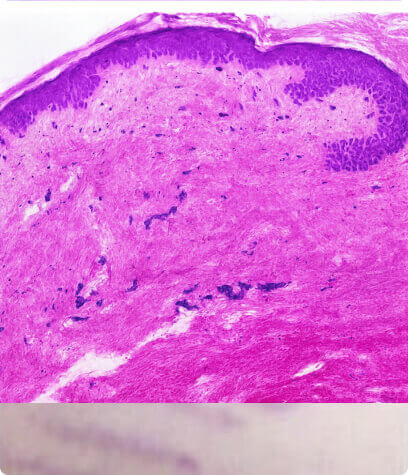

Feine Linien und

Falten

Dieser Alterungsprozess geht mit strukturellen und funktionellen Veränderungen von extrazellulären Matrixkomponenten wie Kollagen und Elastin einher. Dies führt zur Entstehung von feinen Linien und Falten.

Zhang, S., & Duan, E. (2018). Kampf gegen die Hautalterung: Der Weg von der Grundlagenforschung zur klinischen Anwendung. Zelltransplantation, 27(5), 729–738.

So funktioniert es

- Fördert den Abbau von altem, geschädigtem Kollagen

- Es induziert die Proliferation von Keratinozyten, die Wachstumsfaktoren freisetzen, um die Kollagenablagerung durch Fibroblasten und die Elastinablagerung zu fördern.

- Moduliert die Expression mehrerer Gene in der Haut (vaskulärer endothelialer Wachstumsfaktor, Fibroblasten-Wachstumsfaktor, epidermaler Wachstumsfaktor, Kollagen Typ I und III), die die Umgestaltung der extrazellulären Matrix fördern.